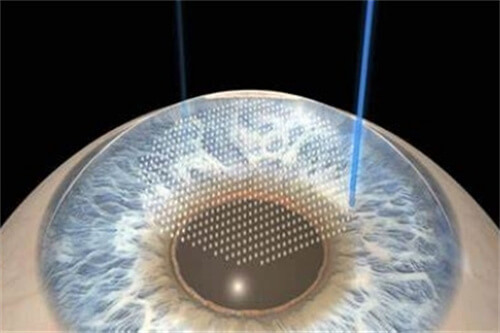

特色技术:医院开展的微切口超声乳化手术,切口仅1.8mm,术后改善比较快,第二天即可获得良好视力。